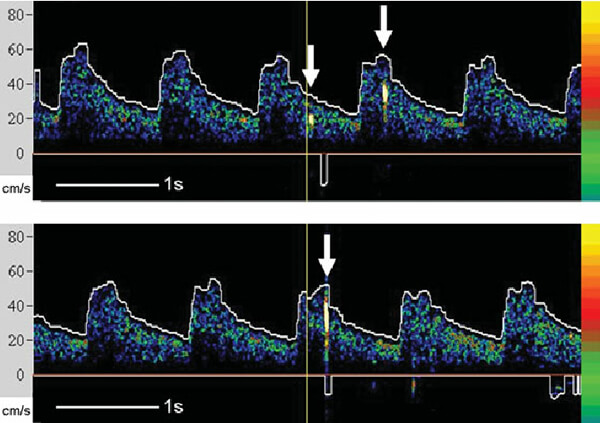

- Σπανιότερα η χρησιμοποίηση του διακρανιακού doppler μπορεί να δώσει πληροφορίες γιά μικρο-έμβολα (υψηλής έντασης παροδικά σήματα) που ανιχνεύονται στην ενδοκράνια κυκλοφορία εξαιτίας μιάς ασταθούς πλάκας με υπερκείμενο θρόμβο. Η ανίχνευση αυτών των μικροεμβόλων είναι ένας πολύ αξιόπιστος δείκτης αστάθειας της πλάκας, άρα και κινδύνου για εγκεφαλικό.